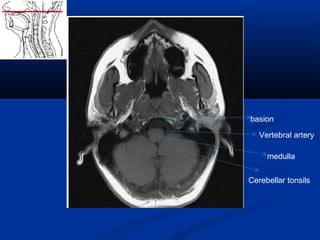

Cerebellar tonsils

medulla

Vertebral artery

basion